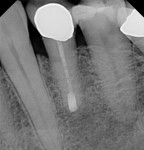

Реплантация зуба: Этапы и особенности операции